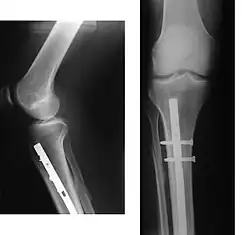

When the initial post-fracture oedema or swelling goes down, the fracture may be placed in a removable brace or orthosis. If being treated with surgery, surgical nails, screws, plates, and wires are used to hold the fractured bone together more directly. Alternatively, fractured bones may be treated by the Ilizarov method, which is a form of an external fixator.

Surgery

Surgical methods of treating fractures have their own risks and benefits, but usually, surgery is performed only if conservative treatment has failed, is very likely to fail, or is likely to result in a poor functional outcome.[42] With some fractures such as hip fractures (usually caused by osteoporosis), surgery is offered routinely because non-operative treatment results in prolonged immobilisation, which commonly results in complications including chest infections, pressure sores, deconditioning, deep vein thrombosis (DVT), and pulmonary embolism, which are more dangerous than surgery.[43] When a joint surface is damaged by a fracture, surgery is also commonly recommended to make an accurate anatomical reduction and restore the smoothness of the joint.

Sometimes bones are reinforced with metal.[45] These implants must be designed and installed with care. Stress shielding occurs when plates or screws carry too large of a portion of the bone's load, causing atrophy. This problem is reduced, but not eliminated, by the use of low-modulus materials, including titanium and its alloys. The heat generated by the friction of installing hardware can accumulate easily and damage bone tissue, reducing the strength of the connections. If dissimilar metals are installed in contact with one another (i.e., a titanium plate with cobalt-chromium alloy or stainless steel screws), galvanic corrosion will result. The metal ions produced can damage the bone locally and may cause systemic effects as well.